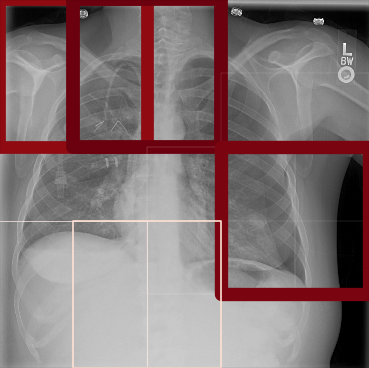

To produce local predictions in the image, the full resolution chest X-ray images are partitioned into overlapping image patches, forming a bag. The goal is to produce a binary classification for each patch where a patch is defined as positive () if it contains pneumothorax and negative () if it does not contain pneumothorax.

Fig. 2 shows a schematic of the proposed architecture. In this architecture, we use the previously discussed ResNet-50 network as patch classifier.

To increase the variability of the available data, we augmented the dataset by translating, scaling, rotating, horizontal flipping, windowing, and adding Poisson noise. Input images for CNN and FCN have been created by cropping a centered patch of from the original images resized to . For MIL we cropped overlapping patches out of the image resized to (cf. Fig. 2). In training, we used the Adam optimizer with default parameters and , a batch size of 16, and exponentially decreasing learning rate (LR). Refer to Table 1 for an overview of the parameters and to Fig. 4 for the receiver operating characteristic (ROC) analysis we performed to assess the model performance.

The pre-trained ResNet-50 was also employed as the patch-level classifier within the MIL approach. We chose the binary cross-entropy between the maximum patch score and the image-level label as the loss function. The batch size was selected as the number of patches per image. We trained with an initial LR of for 30 epochs and achieved an average AUC of 0.930.01 using this method. High patch scores (indicated by thicker red frames, cf. Fig. 5(c)) give a hint on the location of the pneumothorax.